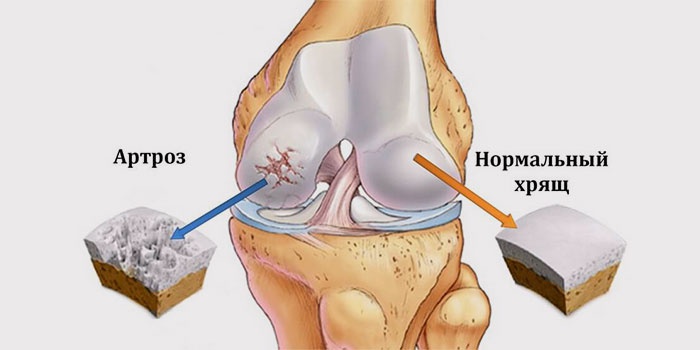

- артроз;

Гонартроз

Захворювання притаманне людям старше 40 років, як правило, частіше страждають жінки. Гонартроз колінного суглоба діагностують у молодому віці після отримання серйозних травм, у професійних спортсменів. Больові відчуття на перших етапах практично не відчутні, з’являються тільки під час руху, наприклад, при спуску, підйомі по сходах. Відчути біль з внутрішньої сторони коліна можна в момент вставання зі стільця. При захворюванні пошкоджень підданий гіаліновий хрящ коліна.

З часом з’являється хрускіт схожий на клацання, який посилюється і стає чути навіть стороннім людям. Після сну ноги складно розгинаються і згинаються, вони здаються онемевшими, а біль посилюється. В суглобовій порожнині з’являються нарости остеофіти, збирається випіт. Якщо шматочок наросту відірветься і застрягне між кісток, він буде провокувати нестерпний біль. Якщо вчасно не вилікувати цей вид артрозу, то його розвиток може привести до знерухомлення ураженого суглоба: хворого чекає інвалідність.